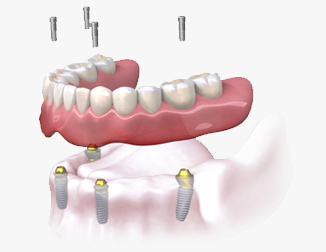

Proteze pe implanturi: Când vine vorba de protezele pe implanturi, există două opțiuni principale:

1. Proteze fixe pe implanturi: O soluție permanentă. Implanturile stabile susțin o proteză fixă sau o punte dentară. Restabilește complet funcționalitatea și aspectul natural al zâmbetului.

2. Proteze detasabile: Acestea sunt susținute de implanturi și pot fi îndepărtate la nevoie. Oferă versatilitate și confort, păstrând totodată sănătatea osului sub proteză.

ÎNAINTE

DUPĂ